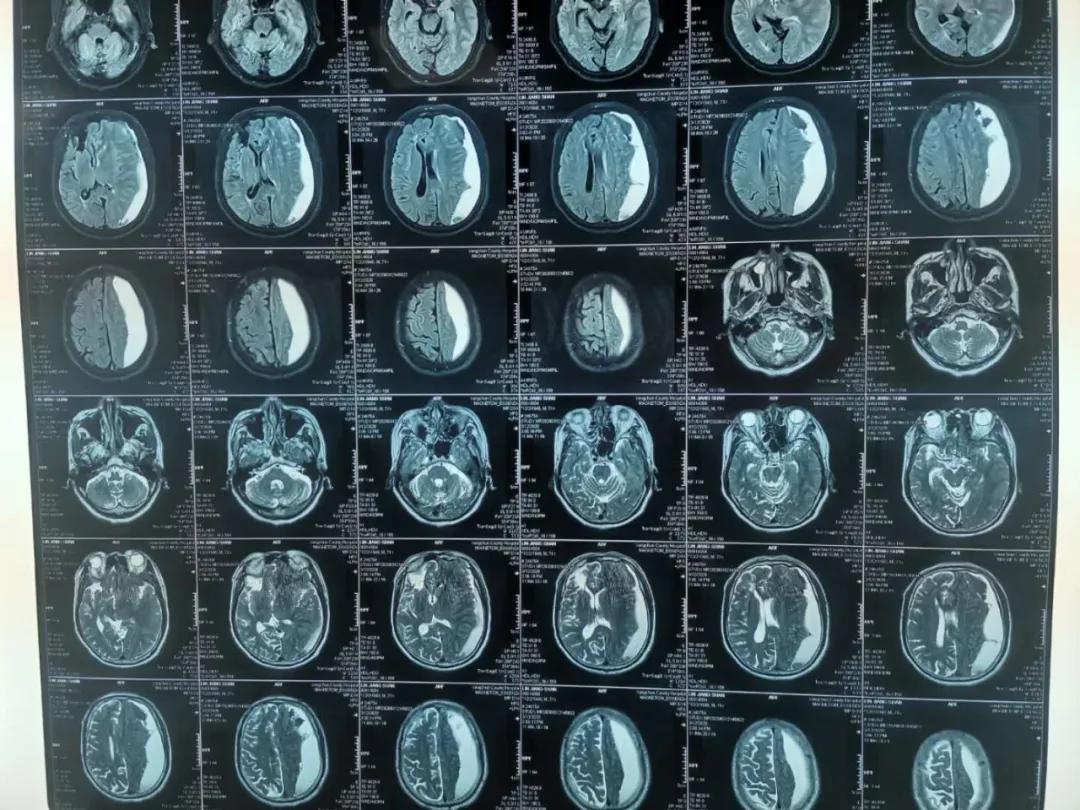

患者林某,男性,82岁,反复头晕半个月,症状时好时坏,未引起重视,未进行治疗,4月27日突发右侧肢体无力,无不能言语,无人事不省,无口吐白沫、双眼上吊、四肢抽搐,无大、小便*禁失**。经查,该患者左侧额、颞、顶部亚急性硬膜下血肿,右侧顶部硬膜下少量出血未除。左侧额颞顶部硬膜下血肿清除术后,于2020.04.28在全身麻醉下行“内镜下颅内血肿清除术+脑积液漏修补术+颅骨修补术”。

术后降低颅内压及抗感染治疗,患者状态良好,病情得到恢复。

术前

术后